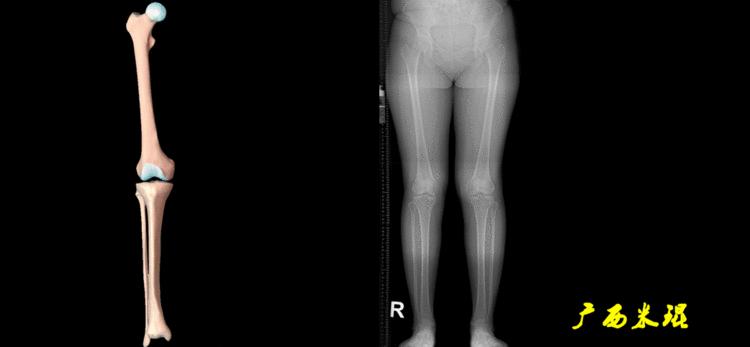

(3)垂直轴

也就是下肢的负重轴,它是身体的纵轴线,与地面垂直,由于双髋比双踝的距离宽,所以垂直轴与下肢力线(机械轴)存在3°的外翻。

开始接触时可能我们对这些轴有点混乱,通过下面的这张图片就能清楚的了解下肢几个轴之间的关系。